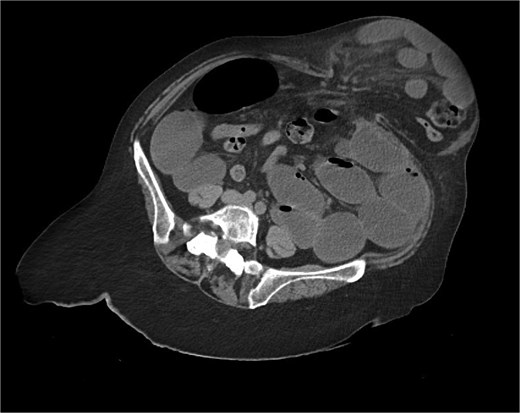

The CT also showed a large ventral hernia in the anterior abdominal wall on the left side, with several entrances and exits for intestinal loops within the hernia. The proximal loops appeared dilated up to 5 cm, with fat stranding and slight fluid between the loops, as well as mild prominence of the mesenteric blood vessels. Distal loops were collapsed, raising suspicion of high-grade obstruction with ischemic bowel involvement (Fig. 5).

CT axial view—obstructed ventral hernia with proximal small bowel loop dilatation.